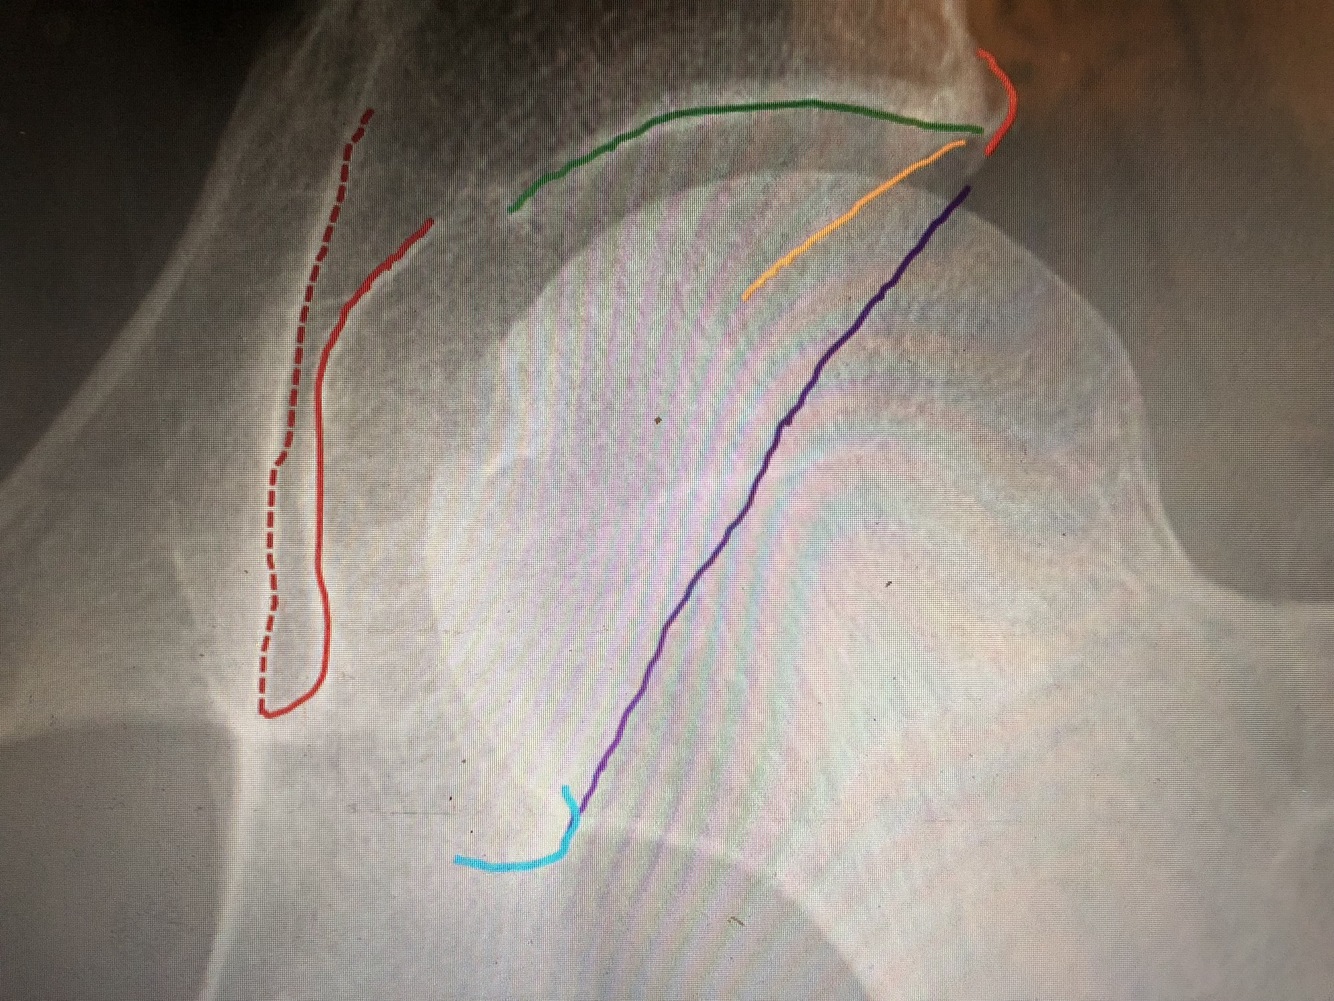

What is the green line?

Medial margin of femoral neck

What is the purple line?

Lateral margin of femoral neck

What is the red line?

most lateral part of Kohler’steardrop is the medial margin of the acetabulum

What is the orange line?

Superolateral margin of the acetabulum

The posterior rim of the acetabulum is more lateral.

What is the yellow line?

The anterior rim of the acetabulum is more medial. (not completely seen)